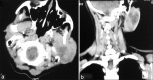

A middle-aged female presented with a painless, slowly growing mass in the left parotid region; fine needle aspiration cytology from the mass showed uniform spindle cells in a fibrillary background with some cells showing palisading. A cytodiagnosis of schwannoma was given, which was further confirmed on biopsy.